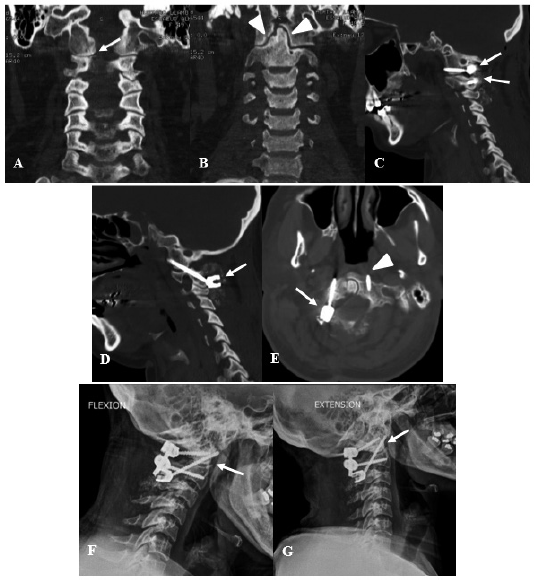

Se consideraron 31 pacientes, con una edad media de 51.16 años con un intervalo de confianza al 95% de 44.9 a 58.1 años, de los cuales 13 fueron mujeres (41.94%) y 18 fueron varones (58.06%). Sobre los antecedentes médicos, lo más frecuente fue la hipertensión arterial en el 29.03% de pacientes, seguido de la osteoporosis en el 25.81% (Tabla N° 1). Luego se procedió al análisis por grupo. Se muestra dos casos representativos de la presente serie en la Imagen N° 1 y N° 2.

El grupo de patología cervical alta más frecuente fue la traumática con 11 pacientes, con una edad media de 40.09 años, siendo hipertensos el 18.18% y diabéticos el 9.09%, un EVA preoperatorio promedio de 6.09 y EVA posoperatorio promedio de 1.91, lo cual tuvo diferencia estadísticamente significativa (p menor de 0.01). Lo más frecuente fue la fractura de C1, siendo el subtipo Landells 2 la más frecuente con el 27.27%. Luego le seguía la fractura de C2, siendo el subtipo Anderson y D´Alonzo 2A la más frecuente con el 27.27%. El déficit motor preoperatorio se presentó en 4 pacientes (36.36%), teniendo una recuperación en el 100% de casos, siendo una recuperación leve en 2 pacientes y recuperación moderada en los otros 2. El déficit sensitivo preoperatorio se presentó en 3 pacientes (27.27%), habiendo recuperación en 2 pacientes (66.67%). El principal tipo de cirugía fue la fijación cervical alta en 9 pacientes (81.82%) seguido del tornillo transodontoideo en 2 pacientes (18.18%). Se presentó 1 complicación que fue una lesión vascular de la arteria vertebral no dominante, que con hemostáticos se pudo controlar. Sobre los resultados posfusión no hubo datos consignados en la historia clínica en 3 pacientes, mientras que en los otros 8 no se presentó pseudoartrosis ni falla del sistema en todos los pacientes (100%) (Tabla N° 2 y 4).

Como se menciona en la literatura, las fracturas del atlas y de la apófisis odontoides son las patologías más frecuentes en el grupo traumático, como se logra evidenciar en nuestro estudio, que llega a tener 7 fracturas de C1 y 4 fracturas de apófisis odontoides, y como se ha descrito, esta patología se trata con fijación C1-C2 o en casos seleccionados con tornillo transodontoideo anterior, tal como hemos encontrado en nuestro estudio que se realizaron 9 fijaciones cervicales altas y 2 tornillos transodontoideos.